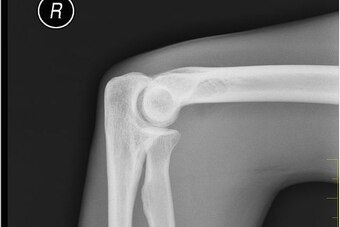

A dislocation describes an injury where one or more bones slip out of place relative to another, disrupting the skeletal system's normal anatomy. For example, a dislocated shoulder involves the bone of the upper arm, the humerus, falling out of the shoulder socket. The very serious dislocated knee occurs when a hit forces the tibia, or shin bone, to move out of alignment with the thigh's femur—either forward, backward or to either side.

In an elbow dislocation, the end of the humerus furthest from the shoulder shifts partly or completely out of place from where it meets both the radius and ulna—the bones of the forearm.